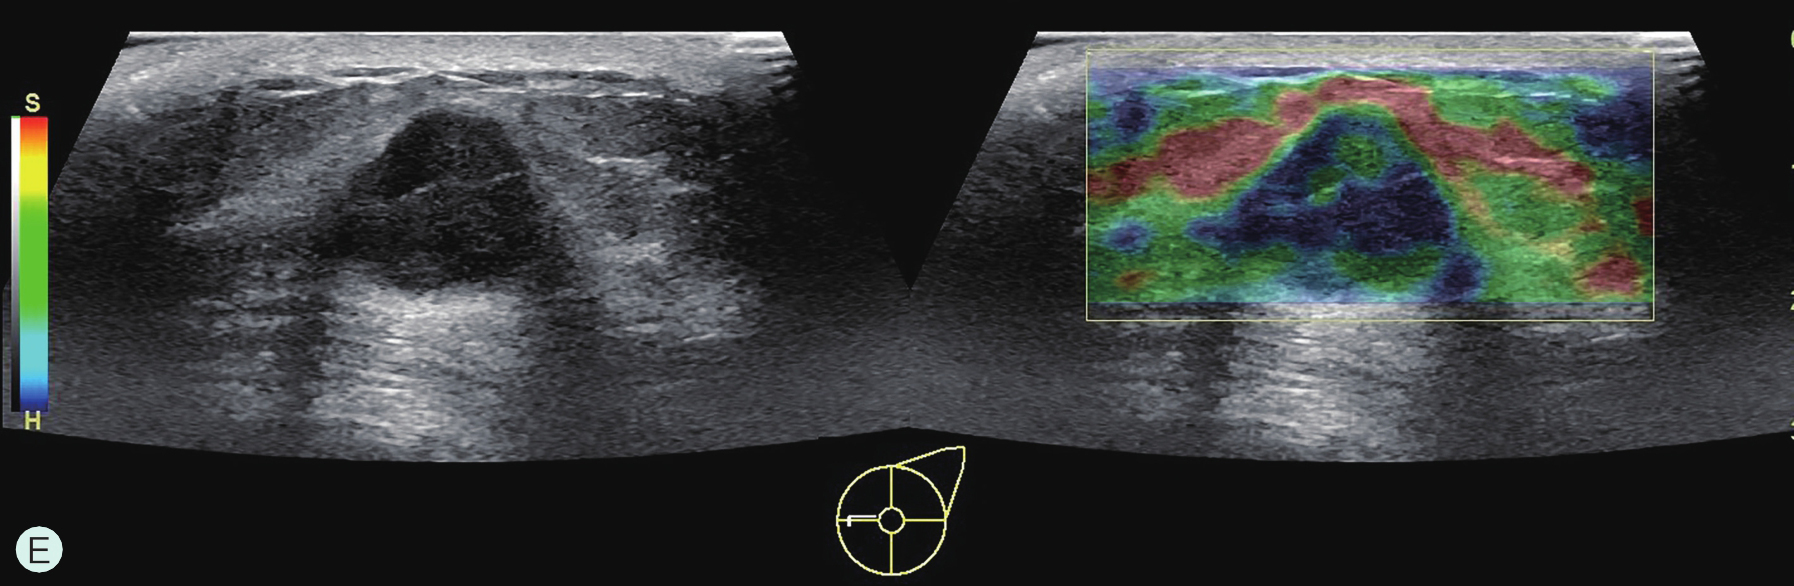

图2-2-1 确定造影病灶

A.病灶二维图像;B、C.病灶CDFI图像;D.同侧腋窝淋巴结情况;E.病灶弹性成像图像

造影前应用传统灰阶超声全面扫查患侧乳腺及腋窝,重点扫查既往检查可疑病灶所在象限,结合既往检查确定超声造影靶目标及造影切面。评估病灶所在部位乳腺腺体致密性,二维及彩色多普勒(CDFI)超声常规检测肿块的大小、形态、边界、内部回声、血流及与周边组织的关系,充分利用现有超声新技术(如弹性成像)全面评估病灶。当病灶位置表浅、位于乳头后方或与探头耦合不佳时,可应用超声垫。

5.乳腺造影增强模式受多种情况影响,与病灶的发展阶段、分化程度、乳腺是否处于增殖期或哺乳期都有关系。如乳腺恶性肿瘤在其发展过程中会经历少血管期、富血管期(图2-2-11),尤其是当肿瘤还较小时,可能新生血管尚未形成,超声造影可表现出等增强甚至低增强,而在富血管期可表现出典型的快进高增强,而有出血坏死时可表现出无增强。同时,在同一非均质性病灶内,不同部位、不同回声类型及不同彩色血流表现的切面,造影也可表现出不一样的增强模式,所以拥有扎实的乳腺普通灰阶超声诊断基础是进行乳腺超声造影的前提。尽管乳腺超声造影表现复杂且多种多样,但基于6类乳腺超声造影良恶性预测模型(详见第三章第三节)进行判读可以解决大多数临床问题。